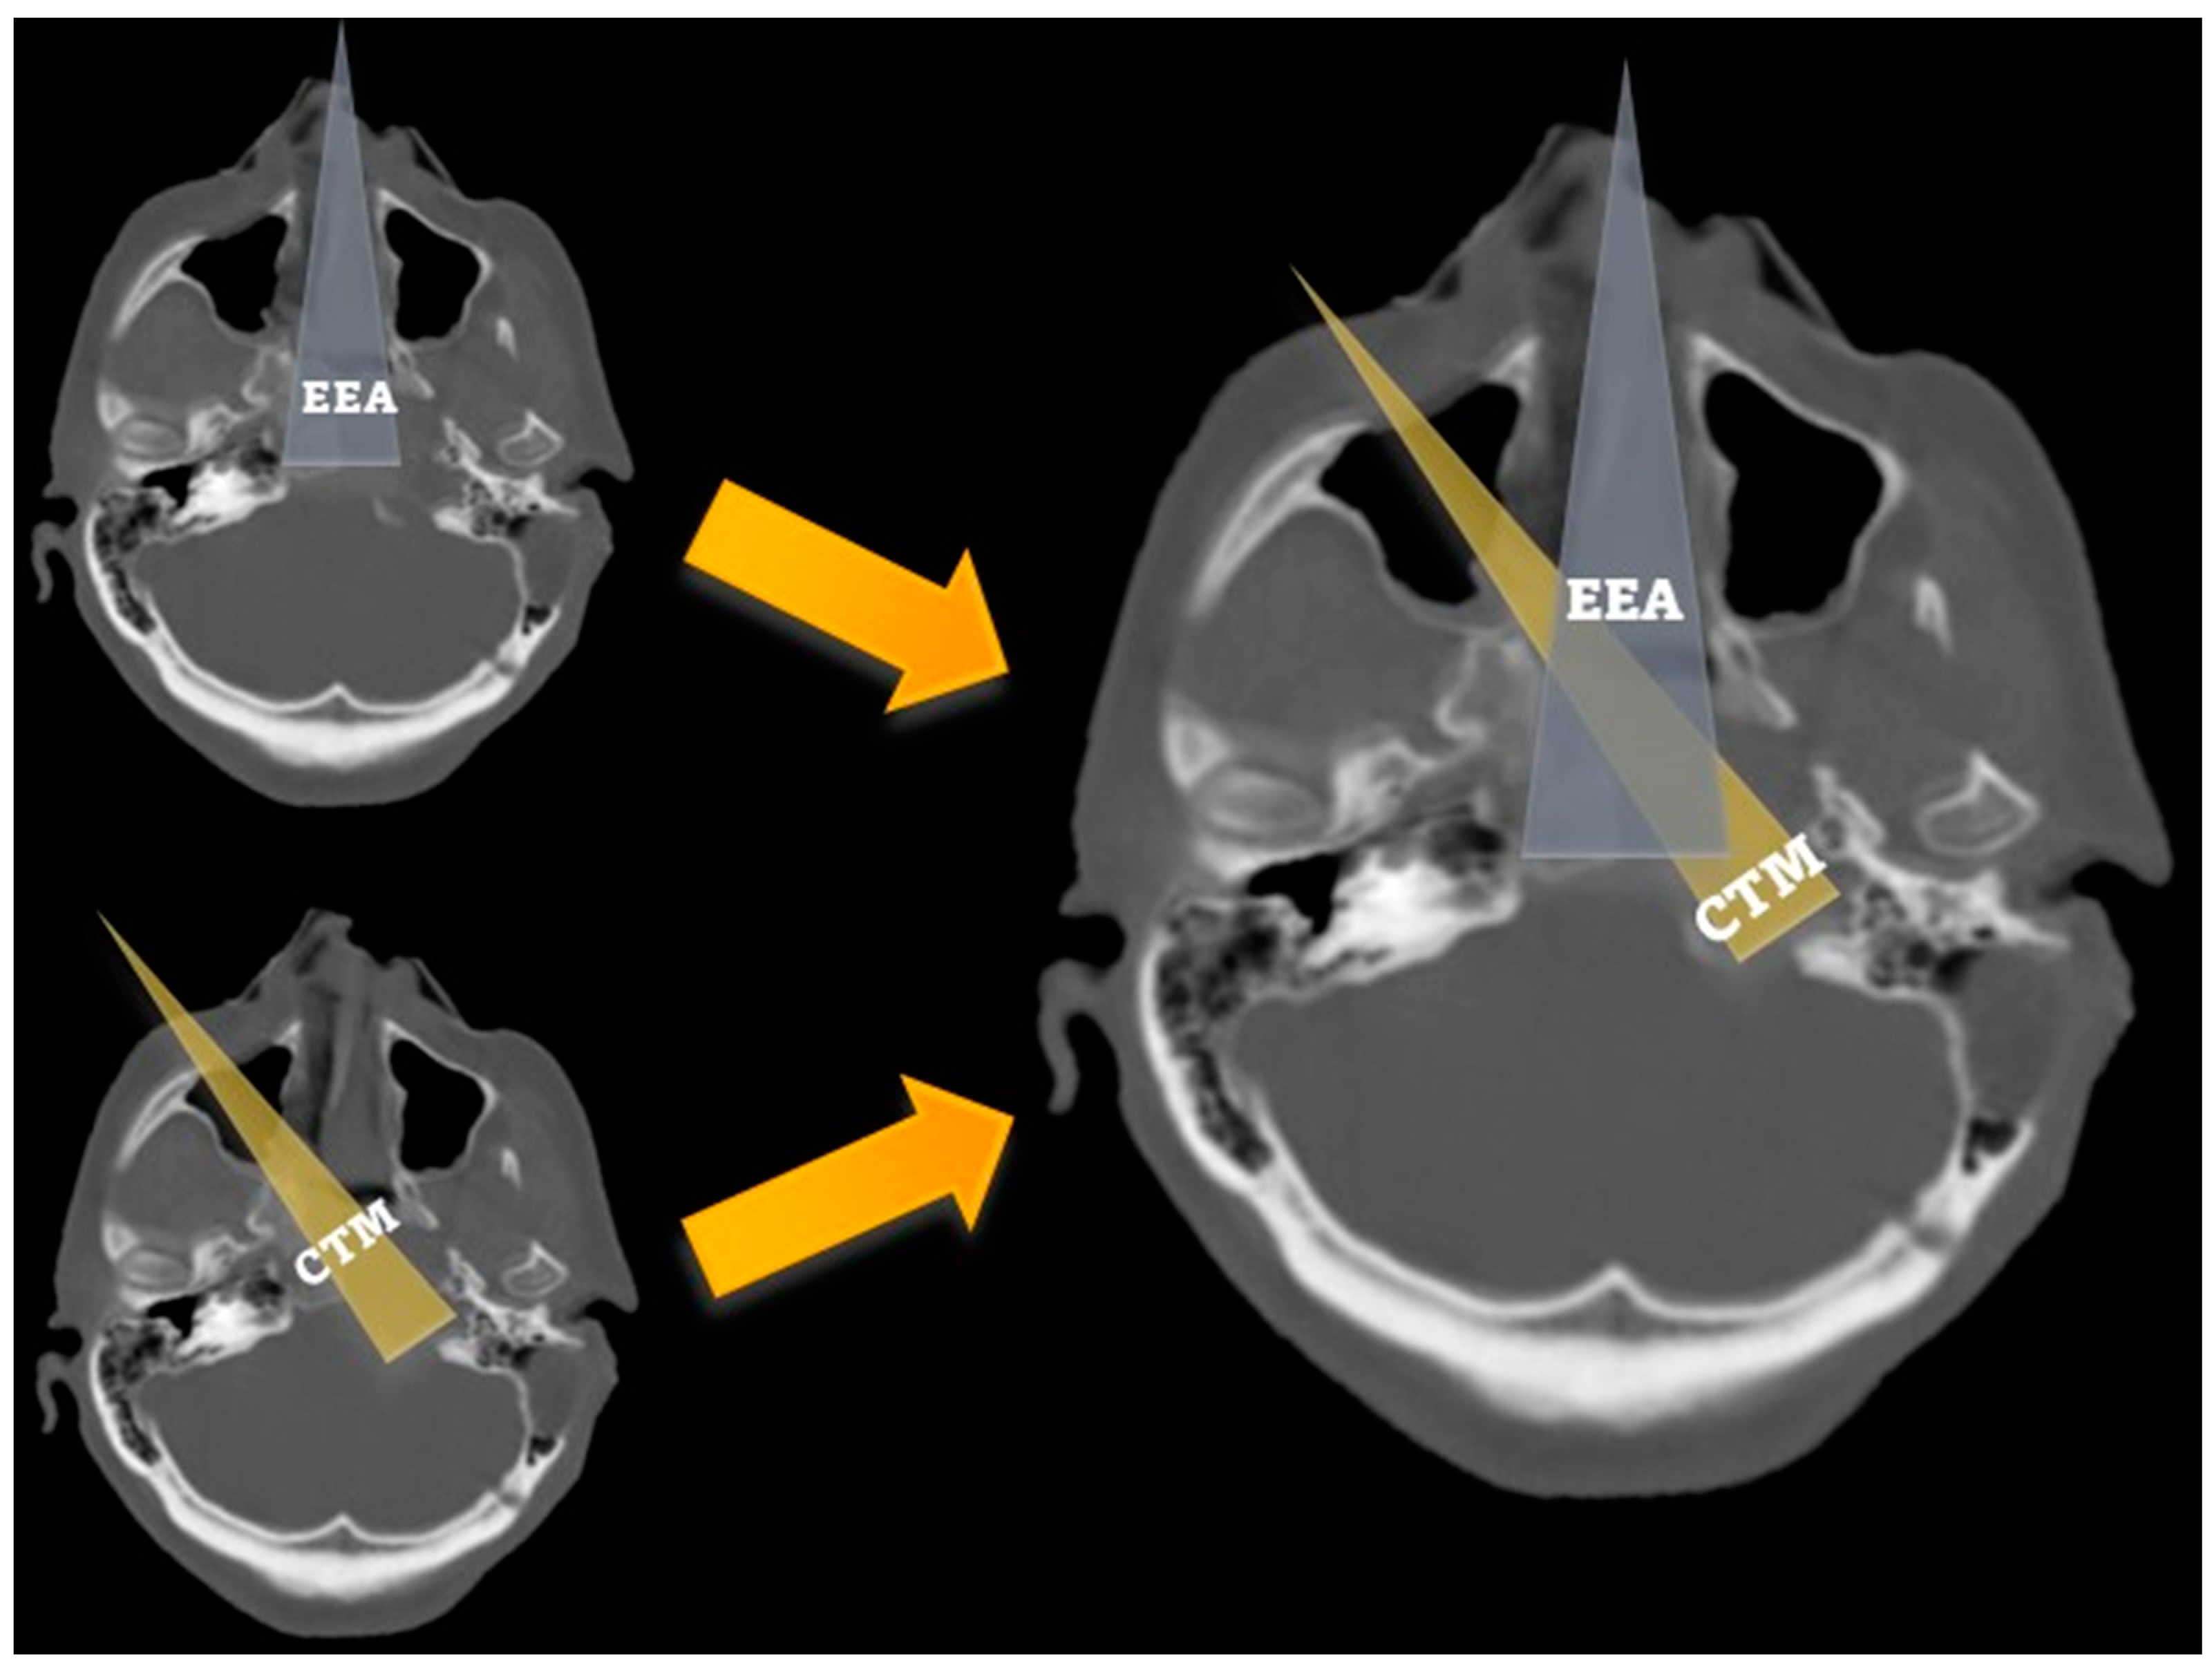

The angle of attack was significantly wider across the transmaxillary than the endonasal route (161.1° ± 8.6° vs. 140.6° ± 5.7°; p = 0.001). The mean gain of angle of attack through the transmaxillary corridor was 20.5° (±4.7°), affording a surgical trajectory more parallel to the major axis of the PA (Figure 5).

Figure 5.

Axial CT scan showing the angle of attack of the endoscopic endonasal (a) and contralateral transmaxillary (b) approaches. A line parallel to the axis of the petrous segment of the internal carotid artery is used as a reference to calculate the angles of attack. MS: maxillary sinus.

As detailed in Table 1, surgical filed depths were significantly shorter (74.3 ± 4.0 vs. 88.0 ± 5.8 mm; p = 0.001) and petrous drilling depths were significantly deeper (17.2 ± 4.0 vs. 11.0 ± 3.3 mm; p = 0.008) through the transmaxillary corridor.

As reported in the literature and confirmed by our findings, the combined EETC and CTM approach affords a significant increase in the angle of attack (between 20° and 25°) relative to the major axis of the PA, exploiting the transmaxillary corridor [7,8,9,10,12]. Moreover, we described significantly shorter surgical field depths across the transmaxillary compared to the endonasal corridor [8]. Overall, the CTM provides a “head-on trajectory” to the PA and PCS and a short distance between the pivot point of endoscopic instruments and the surgical field, considerably furthering surgical maneuverability [7,8,10,12,17]. Consequently, the petrous drilling can be deeper using the transmaxillary as working corridor (Figure 9).

Figure 9.

Bone CT scan comparing the trajectories and the area of exposure related to the endoscopic endonasal (grey) and the contralateral transmaxillary (yellow) approaches, showing that the endonansal corridor provides a good exposure of the medial clivus, while contralateral transmaxillary corridos allow reaching the lateral clivus and the petroclival synchondrosis.